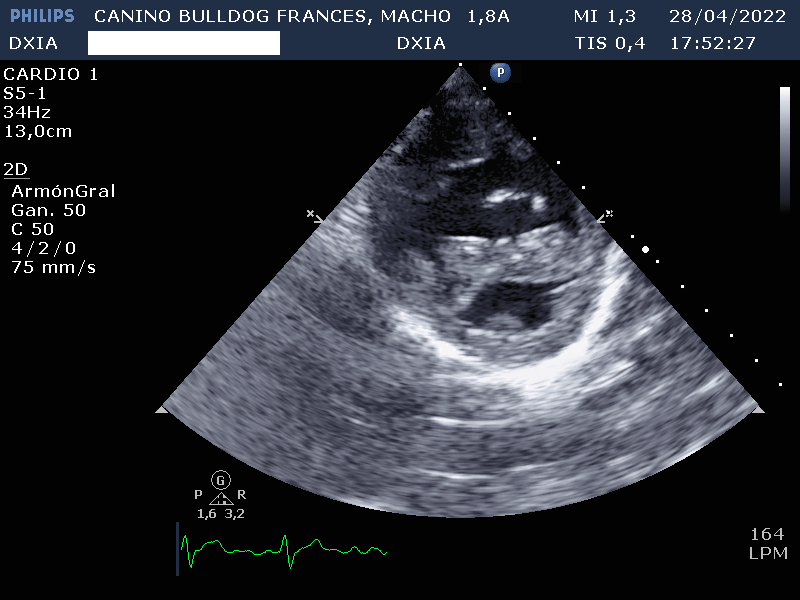

- Válvula tricúspide: Displasia de sus valvas con dilatación severá de AD. Marcado aumento e hipertrofia concéntrica de las paredes del ventrículo derecho.

Por lo tanto el estudio ecocardiográfico es compatible con posible soplo de grado IV en el lado de derecho y displasia de la válvula tricúspide con dilatación severa de AD y VD. Además, presenta estenosis pulmonar severa con leve hipertrofia de la pared del VD.